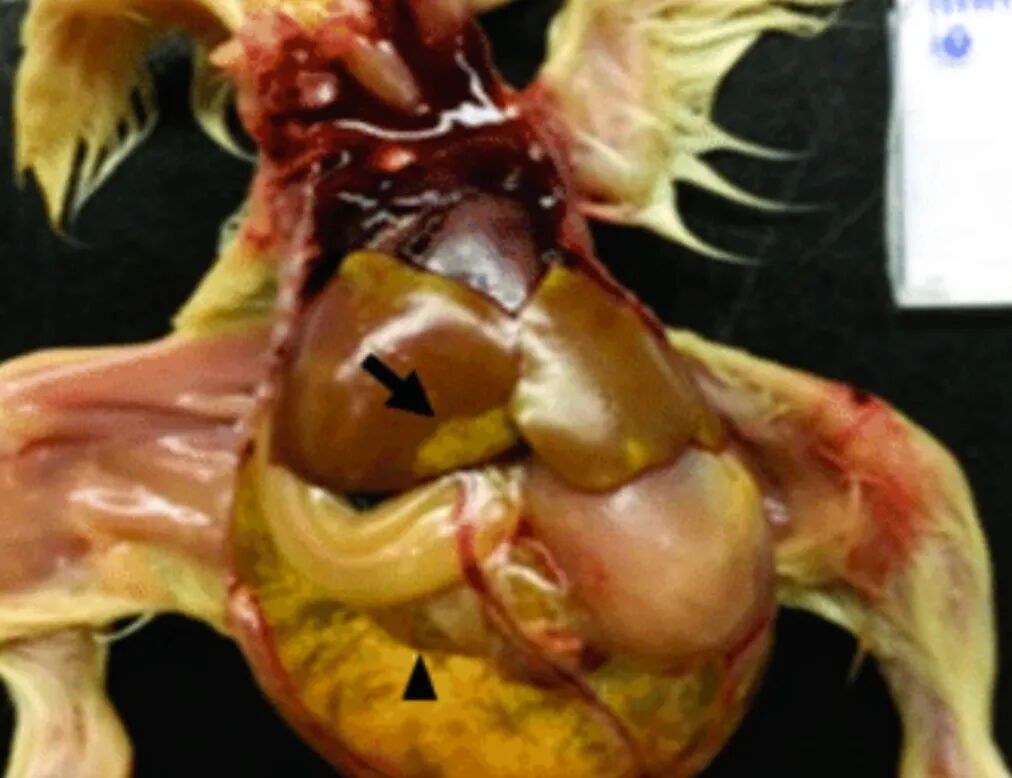

2. 严重肾病与内脏型痛风

部分CAstV毒株具有强烈的肾嗜性。感染后,病毒在肾脏大量复制,导致肾脏肿大、苍白,输尿管因尿酸盐沉积而变粗。严重时,心、肝等内脏器官表面覆盖一层白色尿酸盐,即内脏型痛风,导致雏鸡死亡率显著升高。例如,印度曾报道由B群CAstV引起的痛风暴发,死亡率高达40%。

qw8.jpg